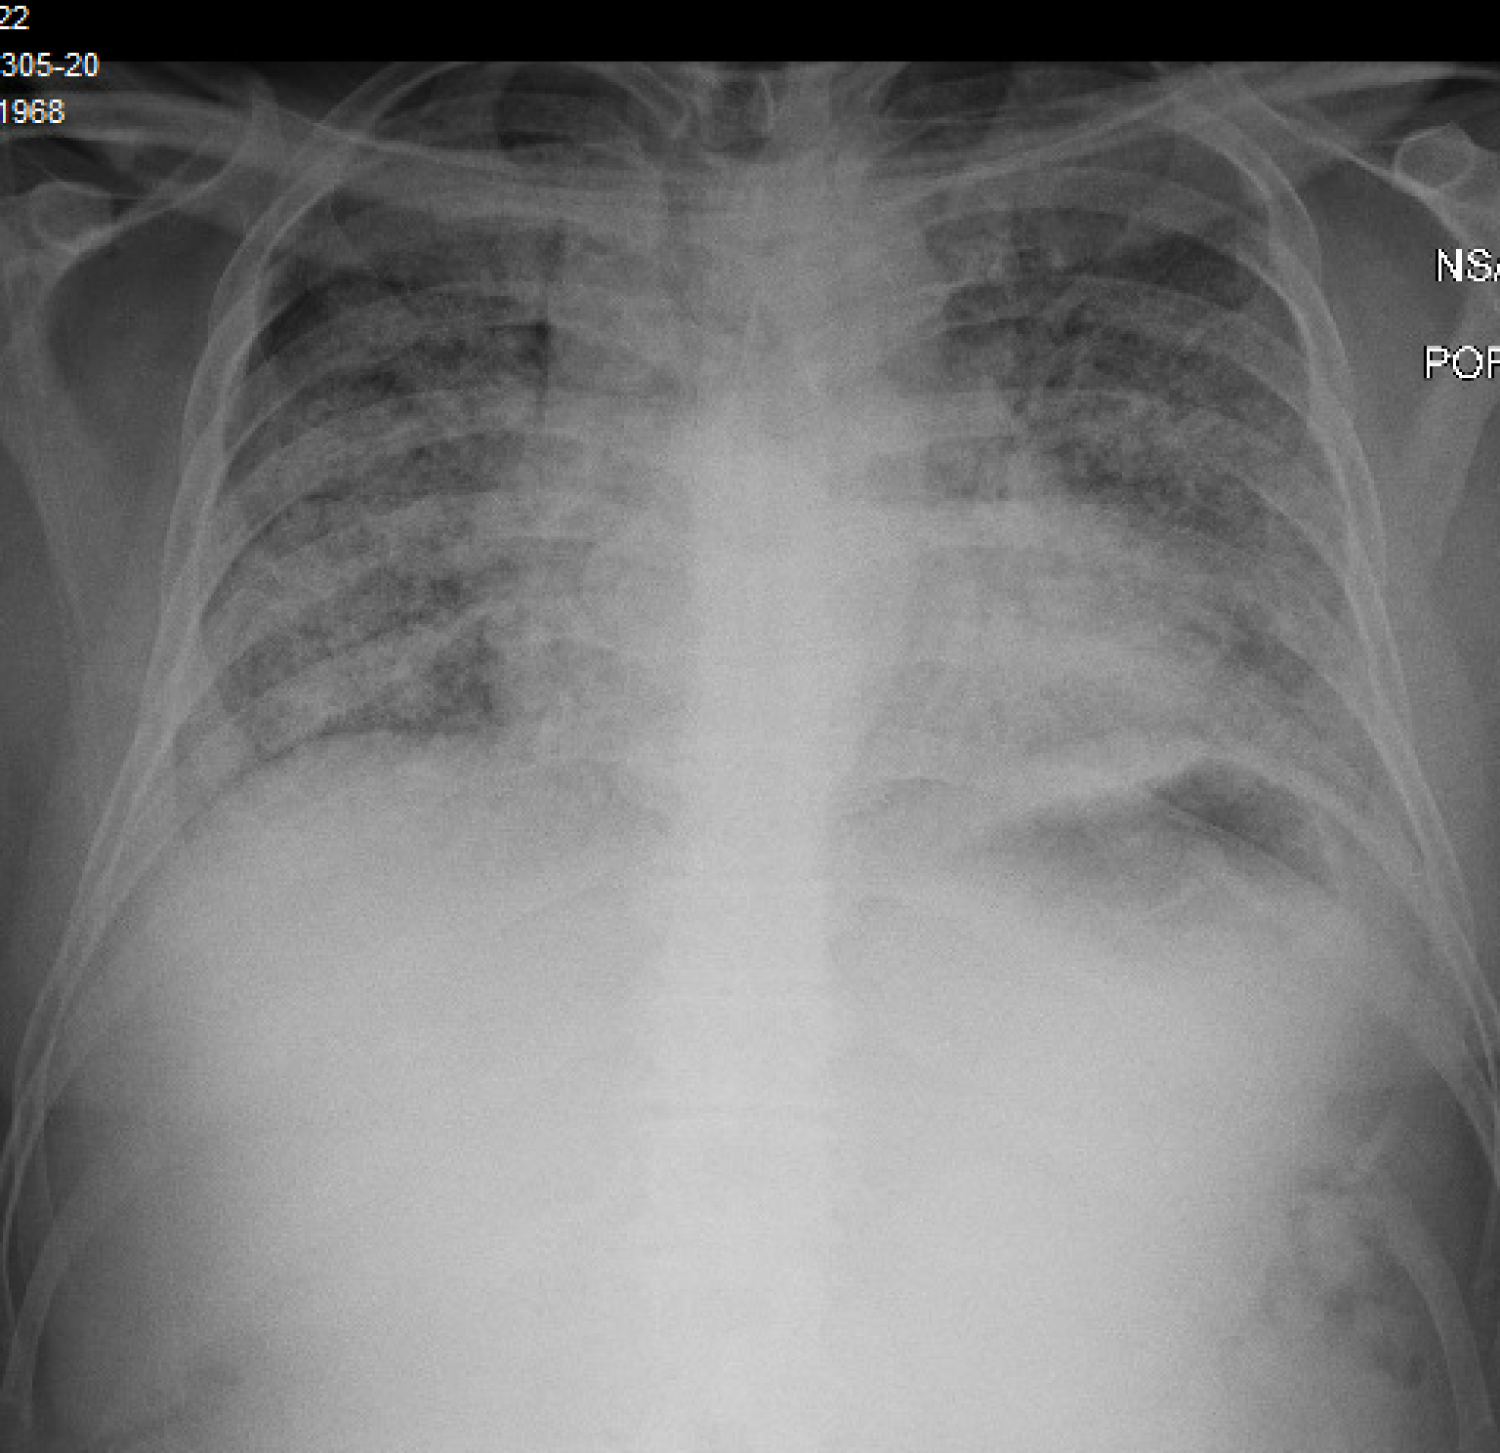

A 34-year-old Hispanic male, never smoker with no significant medical history was admitted with two-week history of non-productive cough, diarrhea, non-bloody, non-bilious emesis and subjective fevers. On admission, he was afebrile, tachycardic with a heart rate of 140 beats per minute, and oxygen saturation 90% on room air and 99% on 4 liters per minute nasal cannula. He was found to have severe Acute Respiratory Distress Syndrome secondary to SARS-CoV-2 viral pneumonia, with a PaO2:FiO2 ratio of 59. Admission labs revealed normal WBC count, lymphocytopenia of 6% and an absolute count of 640/mm3. CRP elevated at 26.9 mg/dL, LDH elevated at 353 U/L, D-dimer elevated at 0.66 ug/mL and ferritin elevated at 478 ng/mL. His chest x-ray revealed bilateral diffuse infiltrates. A CTPE study done by the emergency department to rule out pulmonary embolism revealed patchy bilateral pulmonary consolidation and no evidence of filling defects. There was also no evidence of bullous lung disease. He was treated with a course of hydroxychloroquine, azithromycin, and methylprednisolone. He received tocilizumab and convalescent plasma. His hypoxia worsened during the hospital course, eventually requiring 100% NRB mask and 6 liters per minute nasal cannula in tandem to maintain his oxygenation. On day 18 of his hospitalization, he had persistent hypoxemia with worsening respiratory distress. Patient refused intubation. During the hospital course, he was managed conservatively, and was noted to have slowly decreasing oxygen requirements. On hospital day 36, he developed pneumomediastinum (Figure 3) likely secondary to violent coughing, which eventually improved with conservative management. Chest X-ray done prior to discharge revealed significant improvement in bilateral consolidations and resolution of pneumomediastinum. After six weeks since hospital admission, the patient was discharged home on 2 liters per minute nasal cannula.

Figure 3: Pneumomediastinum. View Figure 3